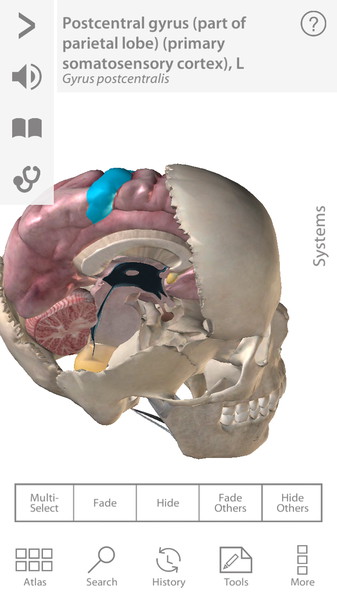

Human Anatomy Atlas 7.4.03

Полностью интерактивный 3D анатомический атлас для Android станет настоящей находкой для всех пользователей, так или иначе связанных с медициной. Врачи и профессора всего мира используют Visible Body 3D Anatomy Atlas, чтобы интерактивно и визуально изучать человеческое тело.

Трехмерный атлас по анатомии рассматривает модели мужской и женской анатомии. Для этого достаточно будет выбрать F или M. Далее воспользуйтесь удобным поиском по системам (Select System) и Вы сможете рассмотреть любое сочетание анатомических образований на черном или белом фоне, прочитать и услышать их полное описание (положение, форму, функциональные и физиологические особенности). Приложение само по себе очень чувствительно. Удивительно то, что при максимальном увеличении изображение не теряет своей детализации. Пользователь в полной мере сможет воспользоваться жестами многозадачности и понимание строения человека будет максимально эффективным.

- Каждая модель содержит порядка 4600 анатомических образований.

- Модель можно вращать, наклонять, приближать – одним словом, изучать под любым углом.